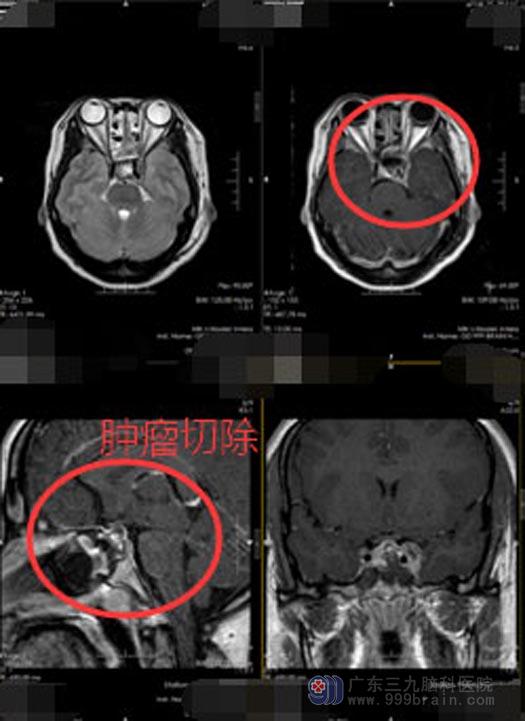

打消了小吴的顾虑后,由医院副院长、神经外五科主任鲁明主刀,在全麻下为她行“内镜经鼻蝶侵袭性垂体瘤切除术”,术中可见垂体位于右侧,沿着肿瘤的假包膜切除肿瘤,最大限度的减少对垂体瘤的损害,肿瘤侵袭左侧海绵窦,左侧颈内动脉被包绕,肿瘤质地坚硬,左侧海绵窦内肿瘤少量残留。术后,小吴的泌乳素水平下降到458 ug/L,双眼视物较术前清晰,头痛也有了缓解。

小吴术后还需要继续药物治疗,手术可以增加肿瘤对药物的敏感性,药物的疗效会比手术前效果更好。